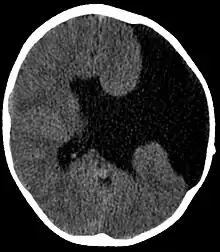

| Axial CT scan showing schizencephaly in a 6-year-old child | |

Schizencephaly (from Greek skhizein 'to split', and enkephalos 'brain')[1][2] is a rare birth defect characterized by abnormal clefts lined with grey matter that form the ependyma of the cerebral ventricles to the pia mater. These clefts can occur bilaterally or unilaterally. Common clinical features of this malformation include epilepsy, motor deficits, and psychomotor retardation.[3]

Schizencephaly can be distinguished from porencephaly by the fact that in schizencephaly, the fluid-filled component is entirely lined by heterotopic grey matter, while a porencephalic cyst is lined mostly by white matter. Individuals with clefts in both hemispheres, or bilateral clefts, are often developmentally delayed and have delayed speech and language skills and corticospinal dysfunction. Individuals with smaller, unilateral clefts (clefts in one hemisphere) may be weak or paralyzed on one side of the body and may have average or near-average intelligence. Patients with schizencephaly may also have varying degrees of microcephaly, Cognitive impairment, hemiparesis (weakness or paralysis affecting one side of the body), or quadriparesis (weakness or paralysis affecting all four extremities), and may have reduced muscle tone (hypotonia). Most patients have seizures, and some may have hydrocephalus.[4]